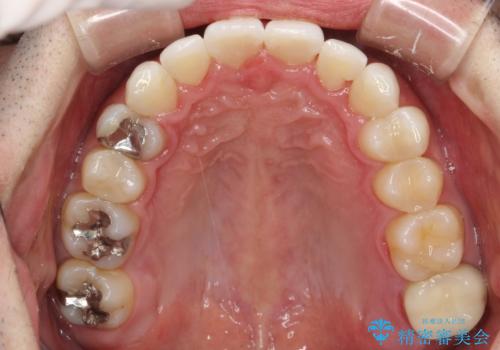

フルリンガル矯正 非抜歯でガタつきを整える

- 30代男性

- 1年6ヶ月

- フルリンガルワイヤーによる非抜歯治療を計画しました。